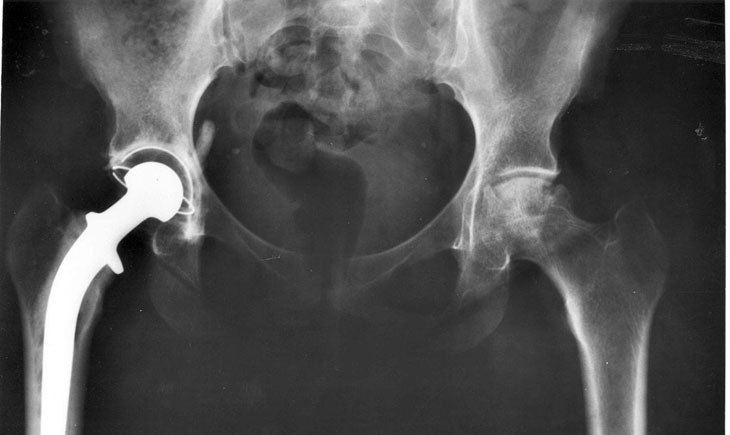

Publiée ce dimanche, cette enquête d’envergure baptisée « Implant Files » a impliqué quelques 250 journalistes issus de 36 pays, dont ceux du Monde, de Radio France et de Premières Lignes, société produisant l’émission « Cash Investigation ». Elle évoque de nombreuses défaillances constatées chez les dispositifs et implants médicaux (pacemakers, valves, prothèses mammaires, prothèses de hanche, stents, pompe à insuline…) et estime que le nombre d’incidents causés par ce manque de contrôle seraient en forte hausse partout dans le monde.

Aux États-Unis, ces dispositifs défectueux ou inadaptés auraient causé la mort d’environ 82 000 personnes et entraîné des blessures ou des complications pour 1,7 millions de patients en l’espace de 10 ans, tandis qu’en France, les fichiers tenus par l’Agence nationale de sécurité du médicament révèlent que le nombre d’incidents liés à ces implants aurait doublé au cours de la dernière décennie, avec plus de 18 000 cas constatés pour la seule année 2017 selon Le Monde.